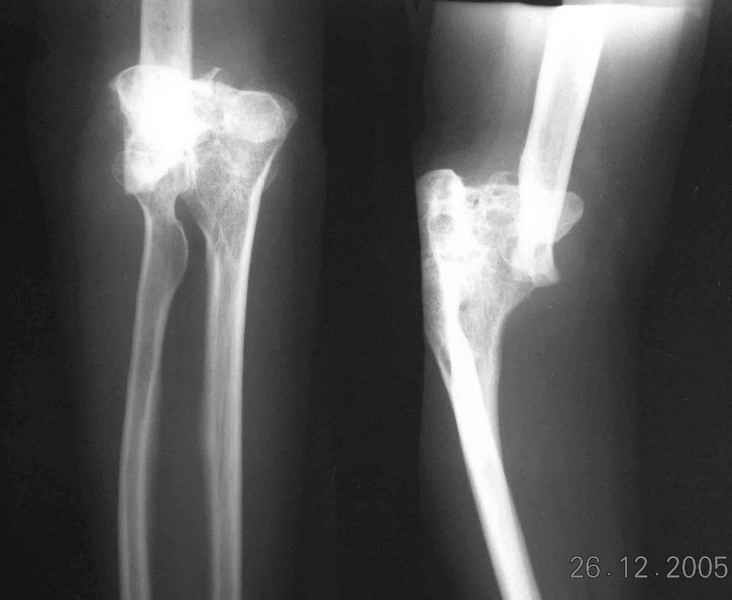

The recent x rays show established Non union with poor quality bone in the distal fragement. The joint is also appearing degenerate. In view of the multiple failed reconstructive surgeries, an Elbow replacement would seem reasonable.

Obviously there is no elbow joint...the options are few: (from the worst to the "best"...if any)